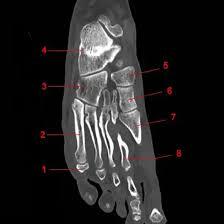

NCCT Left Foot

A NCCT (non-contrast computed tomography) of the left foot is a radiology scan that uses X-rays and a computer to create images of the left foot and its soft tissue injuries. It can help in diagnosing issues like fractures and dislocation in the foot, soft tissue injury, inflammatory arthritis, infections, and trauma of the left foot.